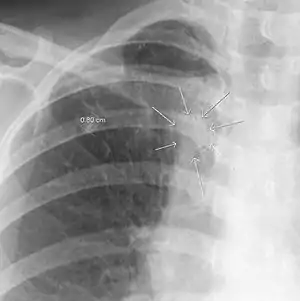

The arrows denote an ill-defined nodular opacity in medial aspect of right upper lobe with ill-defined rim of lucency surrounding it